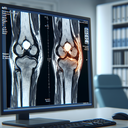

МРТ колінного суглобу

МРТ колінного суглоба – це неінвазивна діагностична процедура, яка використовує магнітне поле та радіочастотні хвилі для отримання детальних зображень структури коліна. Цей метод є особливо корисним для оцінки стану м'яких тканин, таких як зв’язки, м’язи, хрящі та меніски. ### Коли призначають МРТ колінного суглоба: 1...